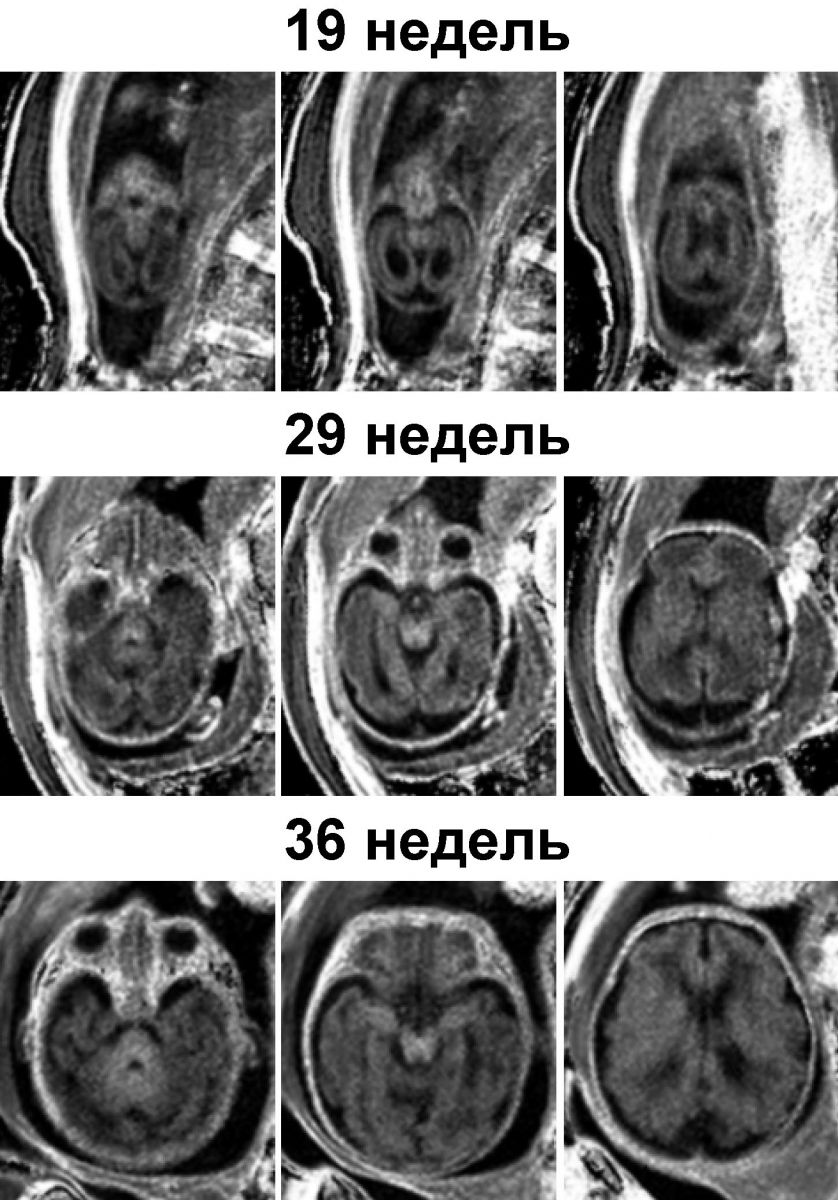

Процесс миелинизации начинается приблизительно на пятом месяце развития плода и интенсивно продолжается после рождения, когда человек учится держать голову, ходить, говорить, мыслить и так далее. Нарушение этого процесса, а также некоторые заболевания (например, рассеянный склероз) могут повредить миелиновую оболочку нервных волокон и таким образом вывести из строя центральную нервную систему. Ученые из Томского государственного университета и Института «Международный топографический центр» Сибирского отделения РАН разработали метод количественной оценки процесса миелинизации мозга плода в клиничесских условиях с помощью магнитнорезонансной томографии (МРТ).

Современные методы МРТ позволяют на качественном уровне оценить выраженные нарушения миелинизации, но не дают возможности измерить точное количество миелина в нервной ткани. Более ранние технологии МРТ также недостаточно чувствительны к малым количествам миелина, которые присутствуют в мозге плода или новорожденного ребенка. Авторы исследования предлагают использовать для этих целей новый метод – картирование макромолекулярной протонной фракции (МПФ). При обычной МРТ источником сигнала являются протоны, содержащиеся в воде, тогда как метод картирования МПФ измеряет количество протонов, входящих в состав клеточных мембран. Благодаря специальному алгоритму математической обработки изображений и протоколу сбора данных, новый метод позволяет выделить сигнал протонов, относящихся к миелиновей оболочке. В предыдущих исследованиях ученые доказали эффективность этого метода для количественной оценки миелинизации, а в новой работе продемонстрировали применение картирования МПФ для визуализации тонких различий в миелинизации анатомических структур мозга плода.

В исследовании приняло участие более сорока беременных женщин на сроке беременности от 18 до 38 недель. Ученые показали способность их метода надежно оценивать пространственно-временные траектории развития миелина в различных анатомических структурах мозга плода. Новая технология позволяет выявлять очень малые количества миелина на ранних стадиях его формирования с высоким пространственным разрешением и коротким временем сканирования (менее 5 минут). Авторы сравнили данные, полученные для мозга взрослого человека и мозга плода и выяснили, что картирование МПФ являтся наиболее чувствительным к содержанию миелина среди всех известных методов МРТ.